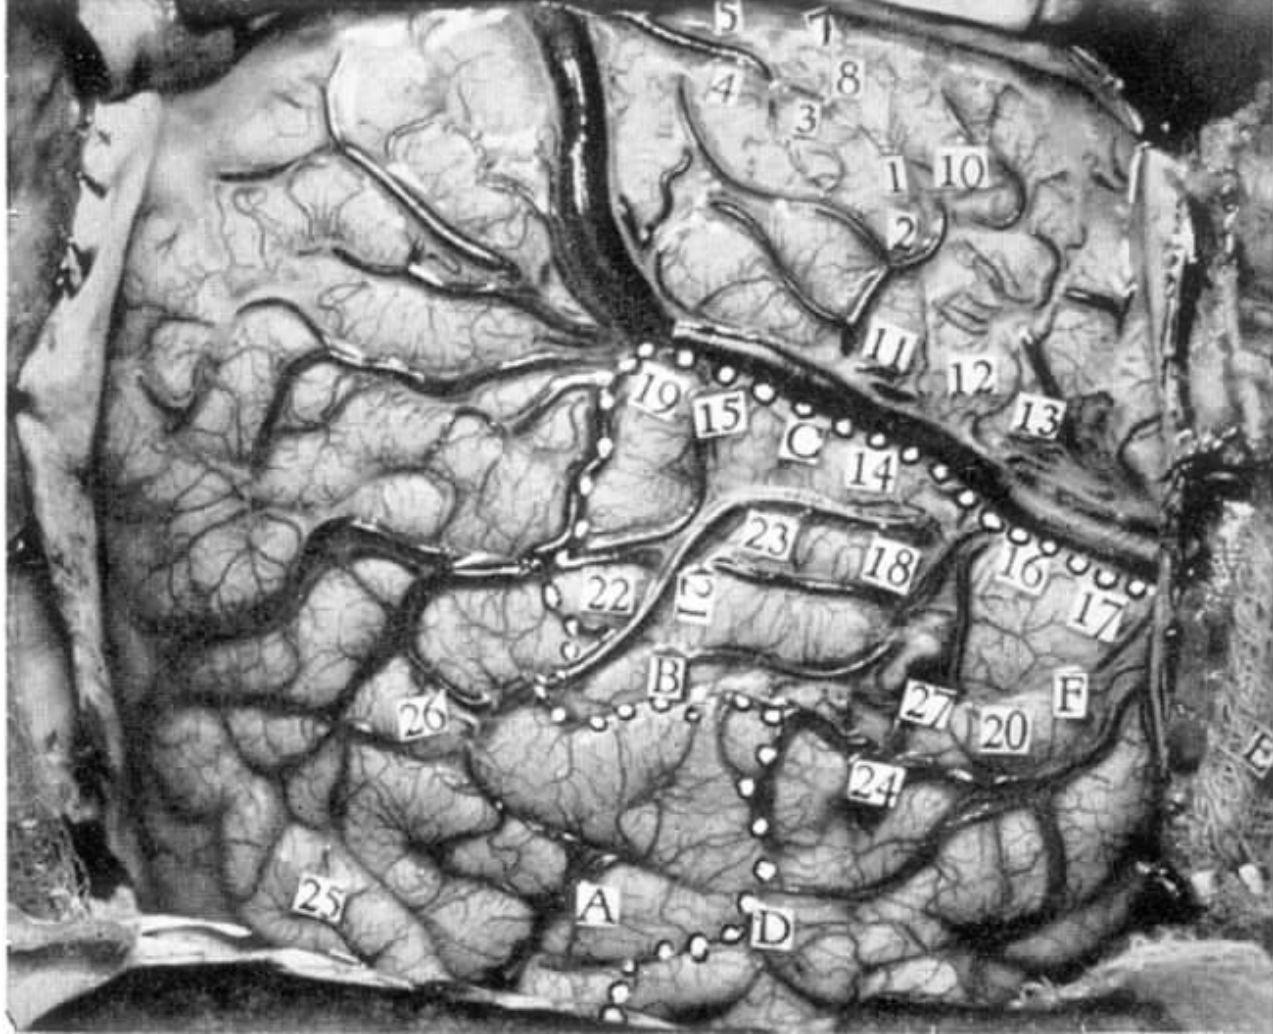

刺激部位

左脑,近中央沟和外侧裂处以及颞叶语言区(图4-8)。

电刺激脑的反应及特点

刺激条件:频率为60Hz的电流(拉姆刺激器),运动和感觉区的起始刺激电压为1V。颞叶皮层的刺激电压增加到2V,接着是3V,最后是4V。使用更强的电流时,患者有时在电极撤除后才能描述(刺激过程中形成的)梦境。

1 发声。

11 计数障碍。

5 右侧上、下唇均出现感觉。

7 右侧下唇出现感觉。

8 舌头右侧近舌尖处出现感觉。

图4-8 病例L.G.去骨瓣的位置已标出(刺激数字所在位置引起的反应详见文中描述;虚线指要切除的区域;刺激点21、20、23、22和26,使患者失语;刺激点19、14、16、17、18和15,使患者回忆和做梦)

10 右下颌的牙齿和牙龈出现感觉。

失语症的种种表现

21 进行刺激的同时,向他出示一支铅笔。他说:“嗒,嗒,嗒……”然后他说那是用来写字的。当刺激结束时,他说出了“铅笔”这个名字。

20 当勺子被展示给患者时,他说那是吃饭的东西。

23 患者不能叫出剪刀的名字。当被问到它是做什么的时候,他不能命名。刺激结束后,他迅速而准确地说出了它的名字。

22 向患者展示一把勺子,他保持沉默。在他面前摇晃勺子,最后他说,“别晃它了”。刺激结束后,他快速地报出了它的名字。

26 患者变得沉默,看起来是在试着为展示给他的手电筒命名,最后,他说,“它是用来发光的。”刺激结束后,他说出了手电筒这个名字。

记忆和梦境

19 患者起先看起来并不能回应,他只能发出一点点声音。当刺激再次开始后,他说,“歌,嗯,歌曲”,之后,他解释说那是他曾经听过的一首歌,当被问到是人唱还是管弦乐演奏时,他只是说他似乎听过。过一些时候,重复刺激点19。患者看起来不能回应,同时,相邻电极上出现后放电。当后放电结束后,他说看见一个小男孩正在和其他人玩,但他不知道他们在干什么。当被问到是否听到歌声时,他作肯定回答。

14 患者说他听到了一些他听过的声音,但看起来他不能描述那些声音。稍后,在无提醒的情况下重复刺激点14时,他起先看起来不能说话,同时,电极上也出现了少量后放电。随后他解释道:有两人坐在扶手椅上唱歌。他否认那首歌他以前听过。

16 男孩说,“有什么东西从我身边过去,我感觉到了。”他解释道那不是他曾经听到过的而是感觉过的。当被问到那是否像癫痫发作一样,他说,“是的,但是发作时更强烈。”

17 刺激的时间比平时稍微延长,而在刺激时,患者一直讲着话,他说到“一个男人在打架”。当被问到是否是他熟知的人时,他说:“不是,是个陌生人。”再问他是否知道打架的另外一个人是谁时,他说他无法辨认出来。晚些时候,当点17被重复刺激时,他说,“是的,一个男人。”稍后他解释道:看见一个男人正在遛狗。当被问到那个男人是否是村上或镇上的人时,他说他只是看见男人和狗。

18 进行刺激时,患者说“是的”,而当电极被撤回后,他说他记不起那是什么了。他想告诉我们但他却记不起来。

15 患者说,“某些过去曾在我身上发生过的事情。”

小结

患者无法描述刺激过程中形成的梦境直至撤除电极。刺激颞叶皮层或邻近区出现言语障碍,回忆或梦境。对颞叶语言区进行刺激表明,该区域与记忆也有关。